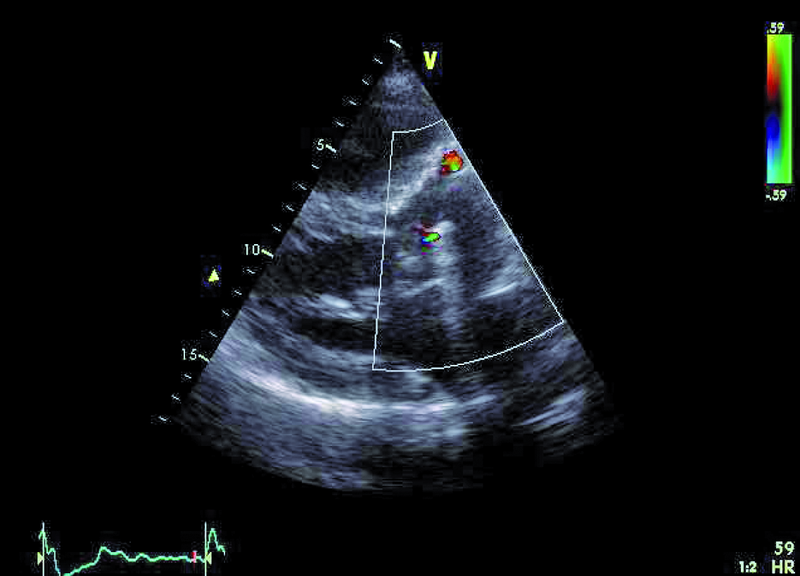

Mężczyzna, lat 35. Jakie patologie można rozpoznać na rycinach?

2. Przeciek okołozastawkowy – przy przednim brzegu pierścienia zastawki aortalnej (ryc. 1, 2).